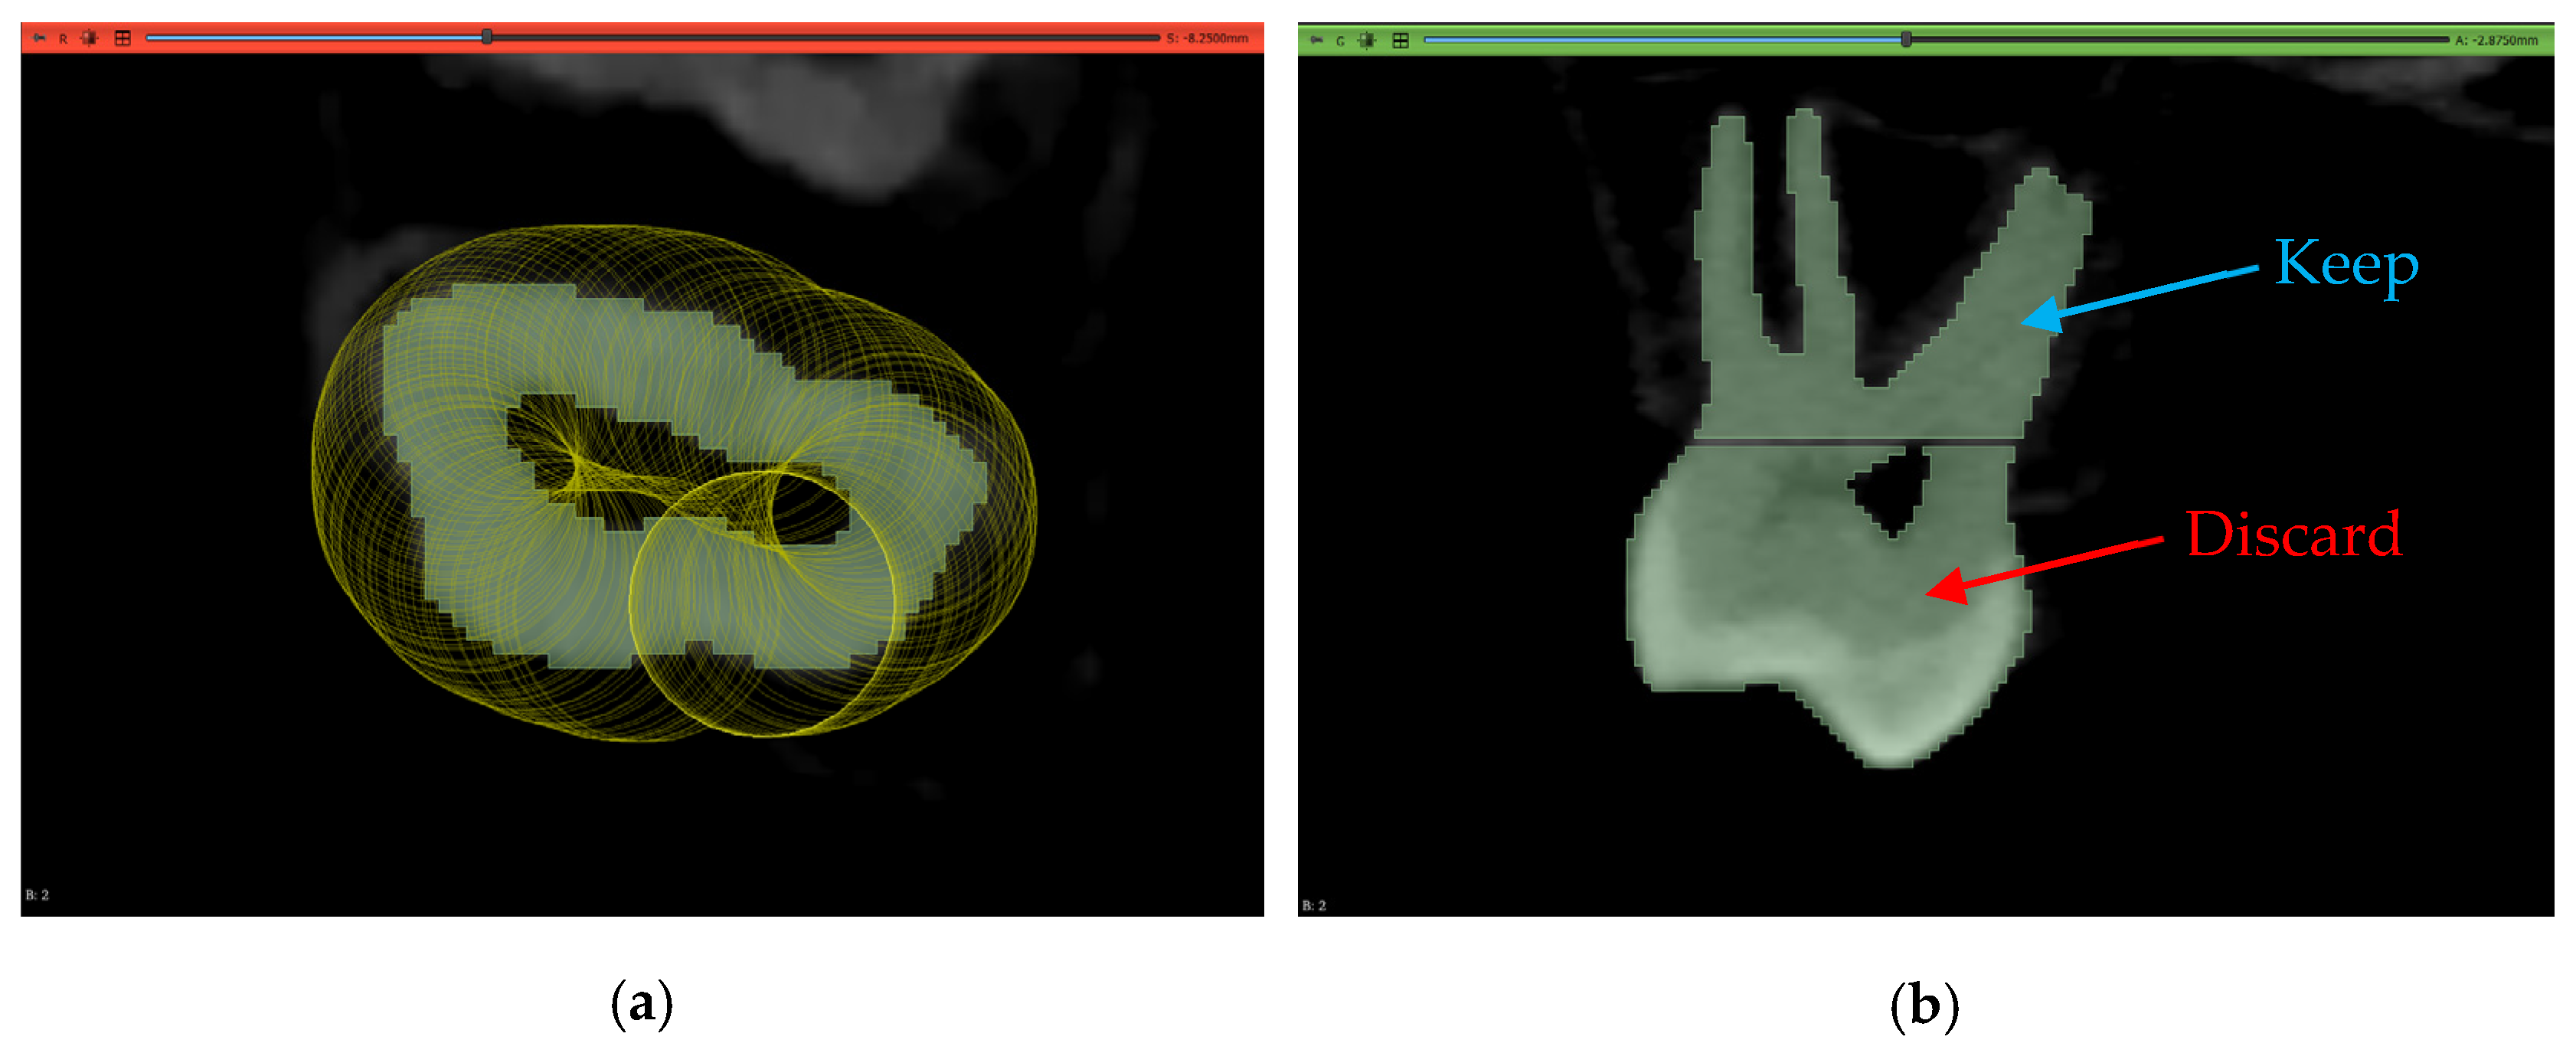

2.3.1. Volume Cropping

2.3.3. Thresholding Masking

2.6. Workflow 3: WS

2.7. Workflow 4: Automated DentalSegmentator